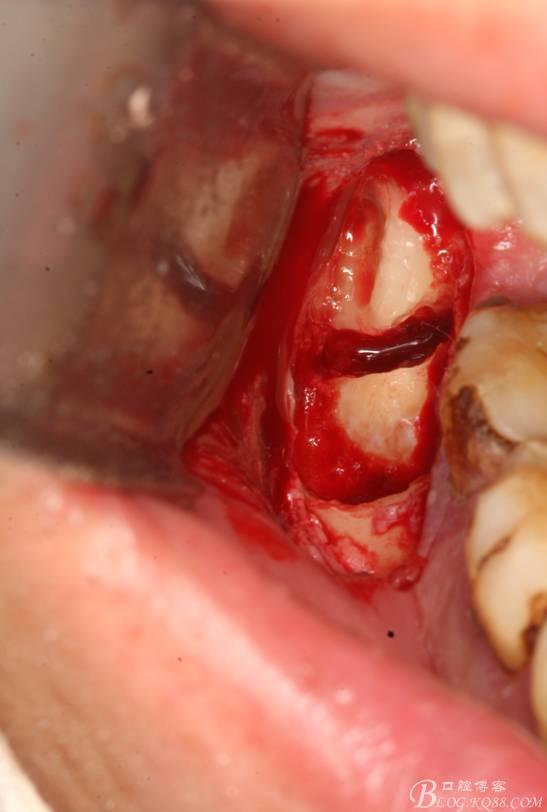

4. 縱分牙根和牙冠

5.取出牙根

6.橫斷牙冠